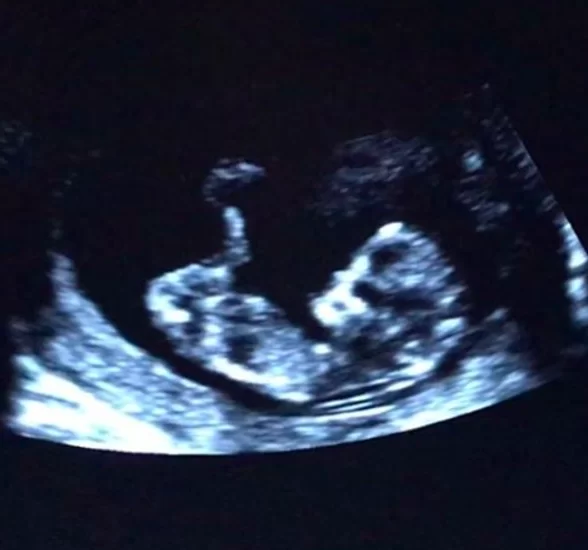

至於杏兒老公Philip除了臉和耳貼在老婆的肚子,他亦在社交網站上載聽肚入面BB心跳嘅照片,又留言:「Happy Mothers Day to the most beautiful mother to be.老婆,第一個母親節快樂!We cannot wait to see you!So for now I will just try to listen to your little heartbeat.」